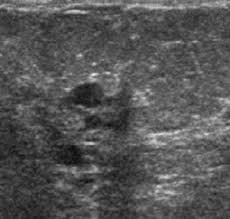

They can also occur in postmenopausal women taking hormone therapy. If the cyst comes back it may be evaluated again with mammogram and ultrasound and it can be drained again. On ultrasound a complex breast cyst will basically be treated in terms of internal echoes presence or absence of posterior enhancement thin septations and a thickened or irregular wall.

Breast cysts do not require treatment unless a cyst is large and painful or otherwise uncomfortable. On ultrasound a complex breast cyst will basically be treated in terms of internal echoes presence or absence of posterior enhancement thin septations and a thickened or irregular wall. A systematic review of the literature on sonographically detected complex breast cysts was carried. Management recommendations for complex cysts were 1-year follow-up in 13 patients 6-month follow-up in 148 sonographically guided aspiration in 82 aspiration with possible core biopsy in 62 and excisional biopsy in three. Your healthcare provider may want to perform a breast cyst aspiration or needle biopsy withdrawing fluid with a needle for analysis. Breast cysts dont require treatment unless a cyst is large and painful or uncomfortable. Not everyone is diagnosed with breast cysts and has treatment before pregnancy or childbirth. Complex breast cysts were estimated to be reported in approximately 5 of breast ultrasound examinations. Breast cysts can also be found in men although this is very rare.